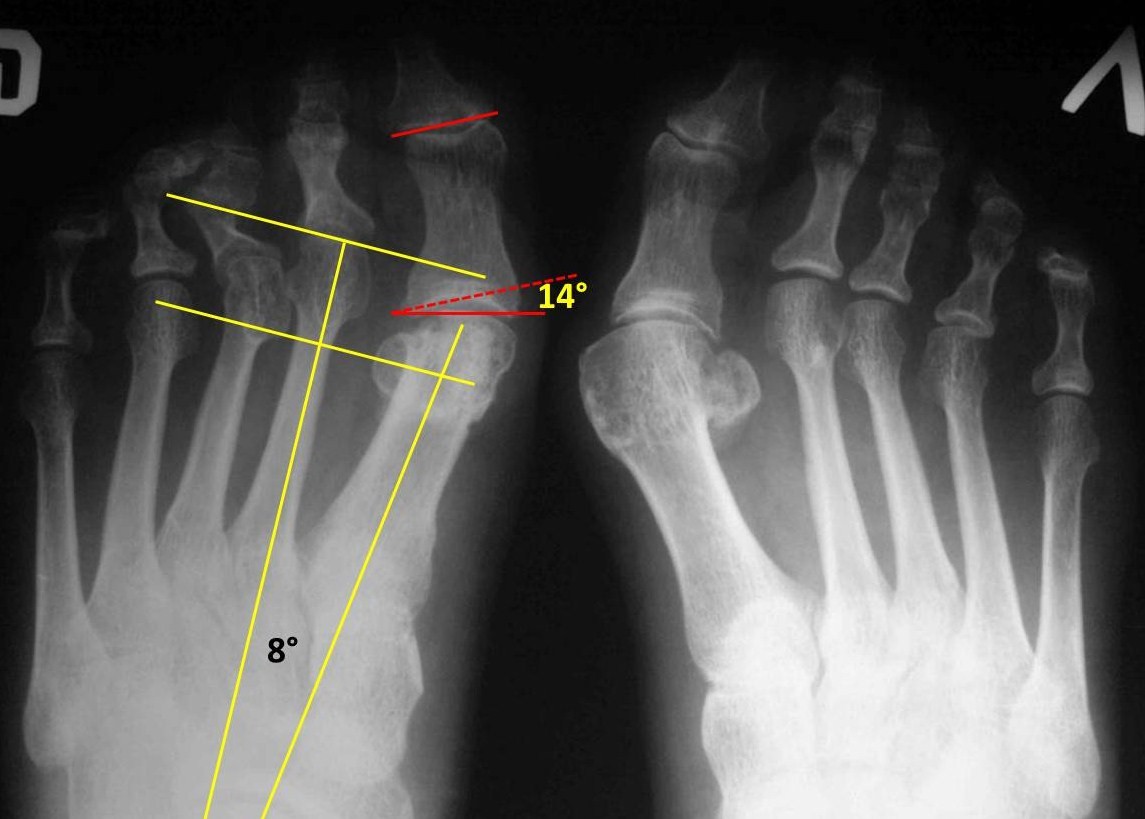

Уважаемые коллеги, обратилась пациентка 55 лет, оперированная около 3-х лет назад в одном из медицинских центров. Операция, видимо, Logroscino справа, похоже, что с аваскуляром головки. Жалоб на первый луч особо не предьявляет, основное беспокойство - молоткообразные 2-3 пальцы, выраженная боль при ходьбе в проекции головок 2-3 плюсневых, омозолелость по подошвенной поверхности. Что на ваш взгляд целесообразно предпринять в данном случае:1.резекция головок с/ф с фиксацией спицей, возможно с Z- пластикой сухожилий разг.? 2. Weil 2-3? 3 резекция головок 2-3 плюсневых? 4. другие комбинации или что-либо другое? 5 нужно ли вмешиваться на первом луче? Сожалею, но других фото в ближайшее время не будетPS Левая стопа недавно оперирована у нас (SCARF), пациентка довольна

С первой плюсневой тут делать ничего не нужно, первый межплюсневый угол всего 8гр. (основные показатели отмечены схематично на рентгенограмме). Но имеется hallux valgus interphalangeus: угол между дистальной и проксимальной суставными площадками основной фаланги 14гр. Его лучше устранить с помощью остеотомии Akin, чтобы первый палец не мешал стать на место второму. Преобладание длин 2 и 3 плюсневых объясняет перегрузку их головок. 4-я плюсневая даже короче, чем могла бы быть относительно первой (перпендикуляр к оси 2 плюсневой, проведенный через середину латеральной сесамовидной кости, в норме должен пройти через середину головки 4 плюсневой. А он проходит выше). Получается, что вмешиваться нужно на 1 луче (дистальный Akin) и на втором с третьим. Задачи, которые тут нужно решить: укорочение 2 и 3 плюсневых (Weil, фиксированный или нет - на Ваш вкус) и устранение молоткообразной деформации 2-3 пальцев. Если она нефиксированная, то достаточным может оказаться подкожной тенотомии разгибателей на уровне плюснефаланговых суставов. Без всякой Z-пластики. А если деформация фиксированная или полуригидная, тогда на Ваш выбор: остеотомия основных фаланг или (хуже) резекция их оснований. Или еще что-нибудь.